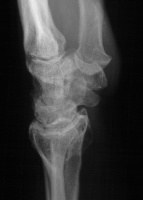

Preoperative Xrays:

Radioscapholunate fusion is a treatment option for radiocarpal arthritis following distal radius fracture or associated with rheumatoid arthritis. Range of motion is usually less than half of normal following this procedure. Technical modifications to improve range of motion include distal scaphoid excision, or as in this case, triquetrum excision and excision of distal ulnar articular surface to manage ulnolunate abutment. There are a variety of fixation techniques. In this case, crossed Herbert screws were used: dorsal carpal bone to palmar radius and dorsal radius to palmar carpal bone.